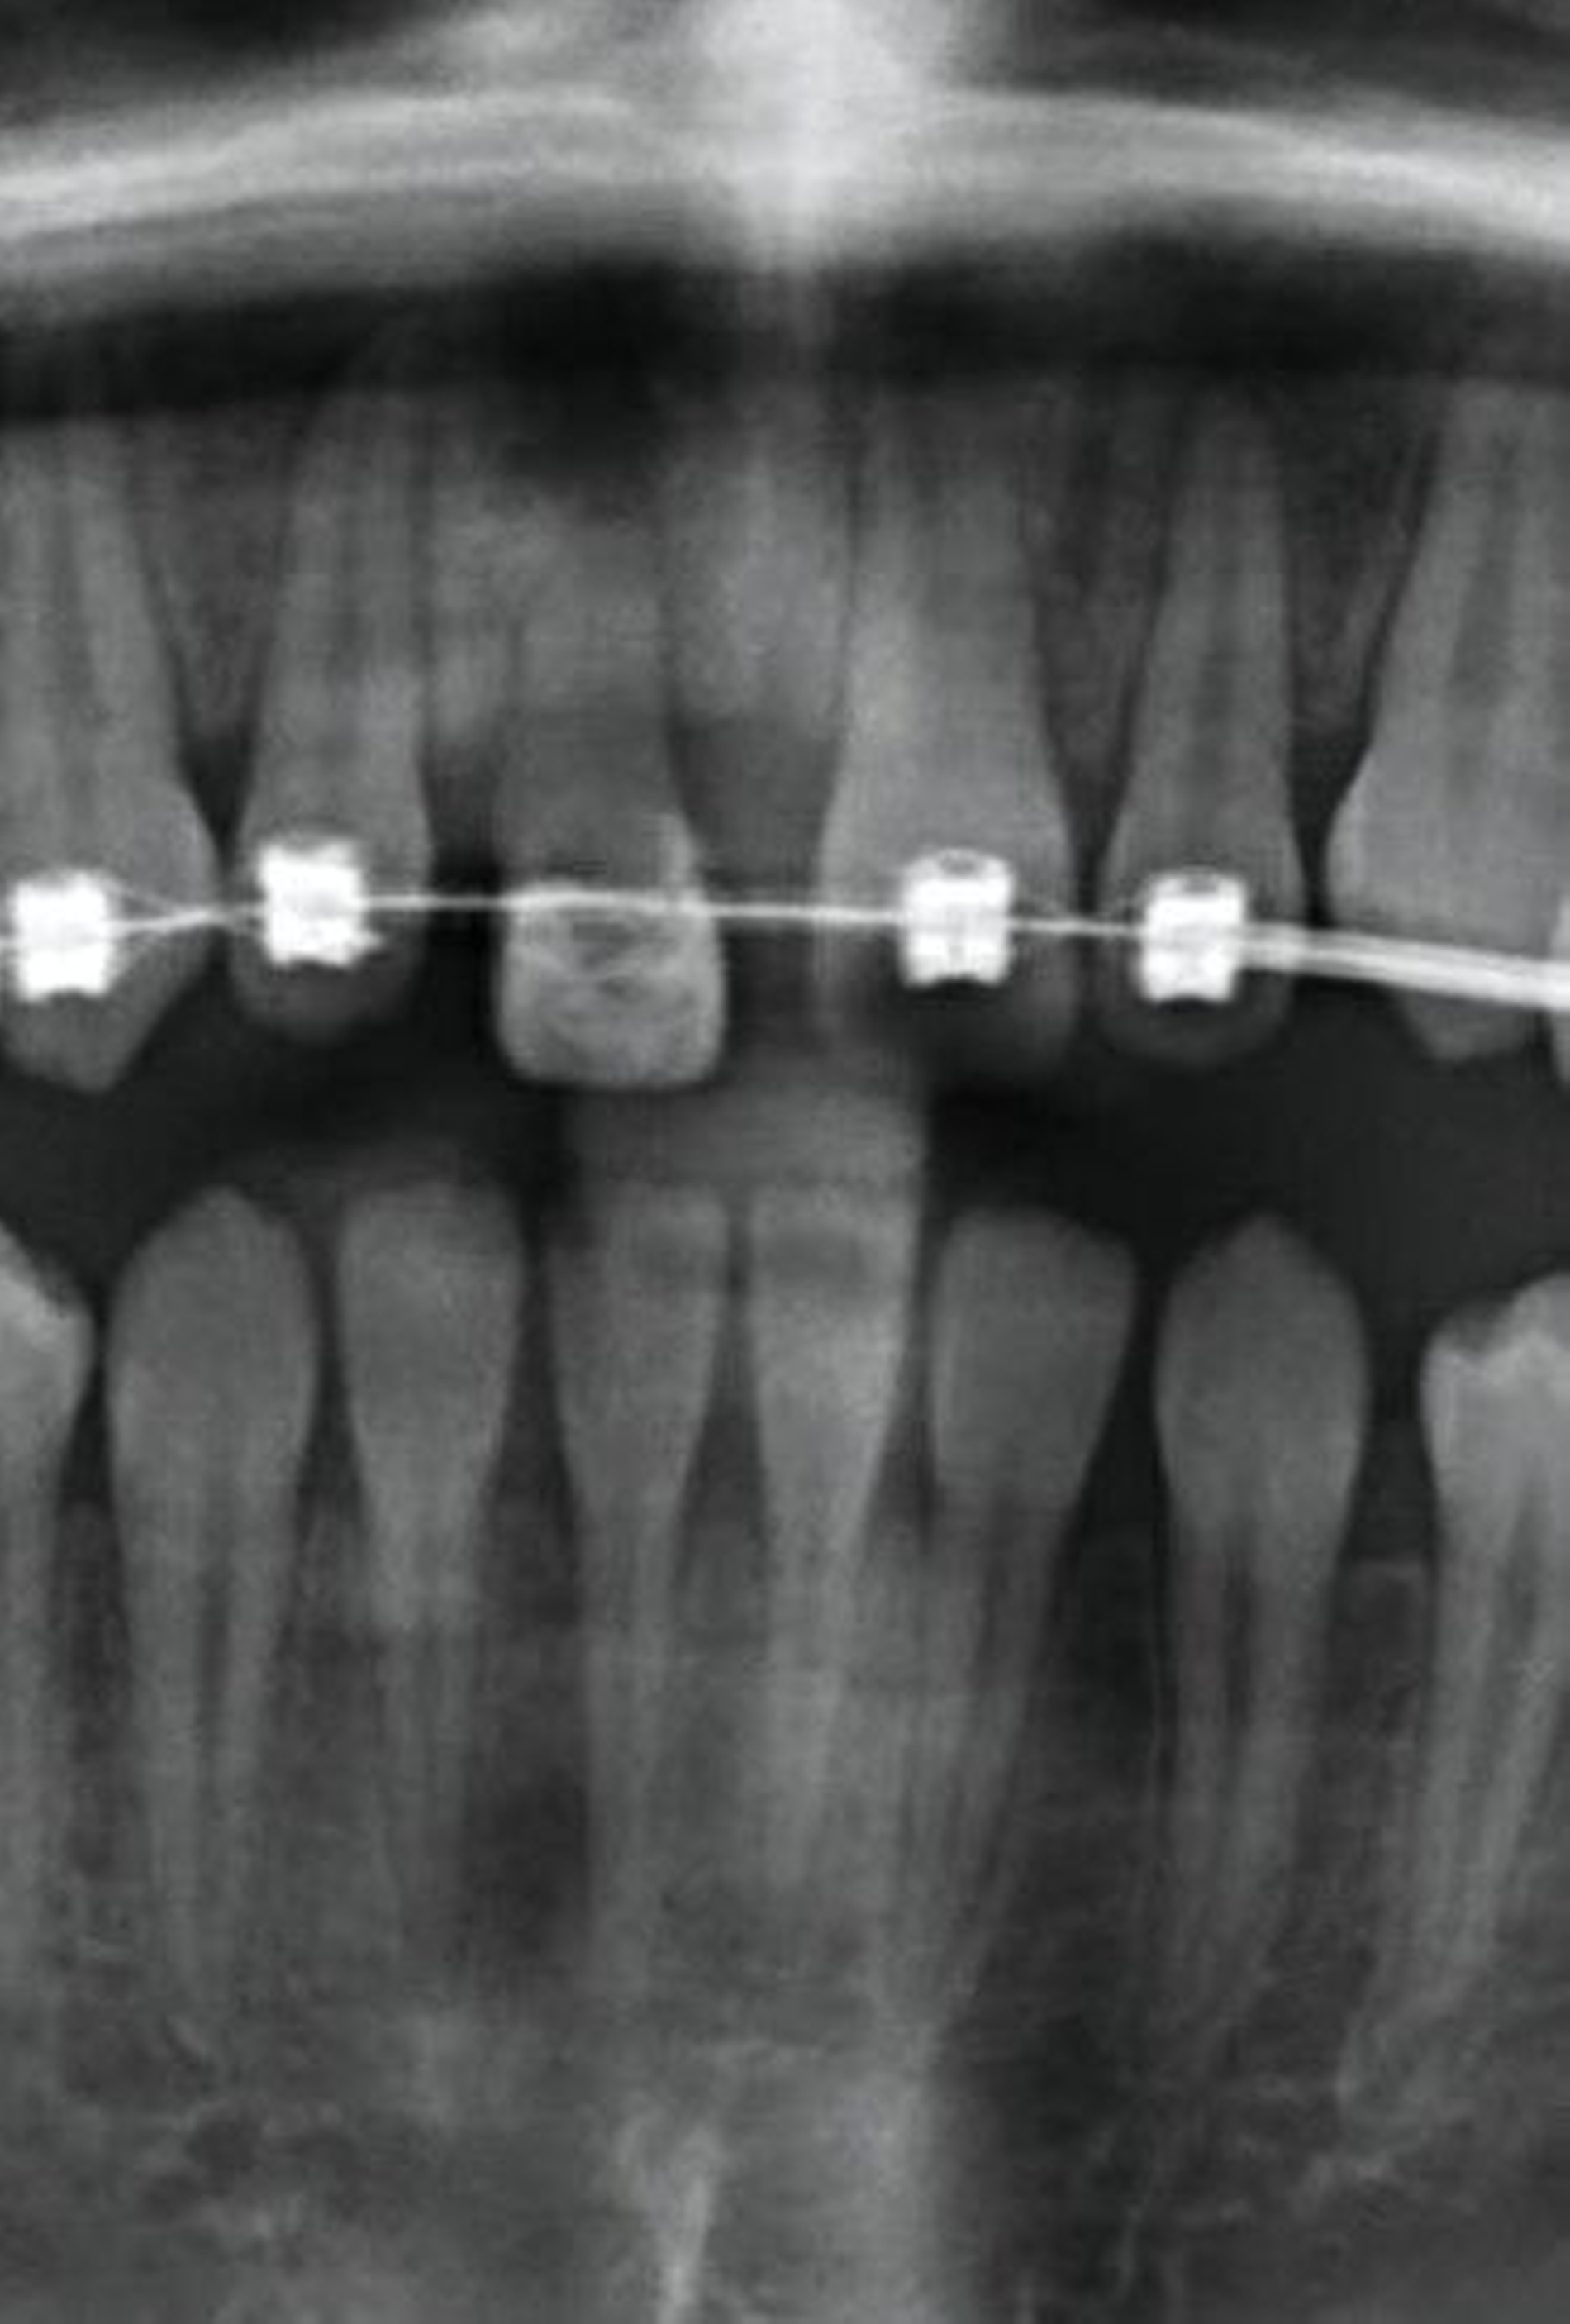

Nach der Einschätzung der Zellvitalität auf der oben genannten Basis folgt die therapeutische Intervention im Sinne der Replantation des betroffenen Zahnes in die gespülte Alveole (vorsichtige Entfernung des Blutkoagulums) mit steriler physiologischer Natriumchloridlösung. Schließlich muss die Replantation schonend erfolgen, da immer mit daran gedacht werden muss, dass es im Rahmen des Traumas zusätzlich zu einer Schädigung des Alveolarknochens gekommen sein kann (Abbildung 1). Diese Schädigung kann eine vollständige oder teilweise Alveolarfortsatzfraktur sein, die entsprechende Beachtung finden sollte. Im Anschluss erfolgt die Schienung des betroffenen Zahnes an den Nachbarzähnen. Dabei sollte ein Zeitraum von ein bis drei Wochen eingeplant werden (Tabelle 1).

Die Replantation sollte langsam und mit wenig Druck erfolgen, um eine zusätzliche Schädigung des Wurzelzements zu vermeiden. Anschließend sollte eine flexible Schienung des Zahnes erfolgen (Empfehlung 50) [Kahler et al., 2016].